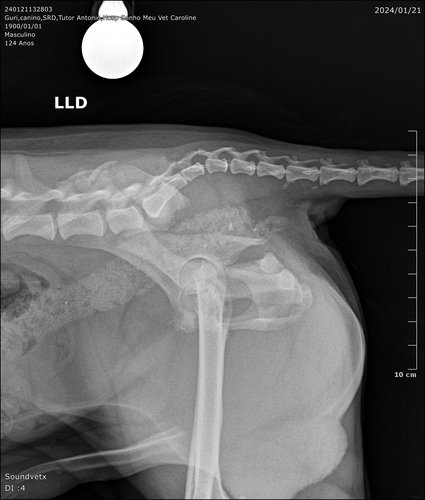

Estou aos cuidados da Dona Malu e alguns vizinhos do Condomínio Vivaz santa Fé esta me ajudando com carinho e doações de remédios. Preciso realizar uma cirurgia pois estou com múltiplas fraturas no fêmur.

Orçamento cirurgia Guri

R$ 1.380 - estabilização de fratura de ílio direito + estabilização de disjunção sacroilíaca esquerda (material ortopédico incluso).